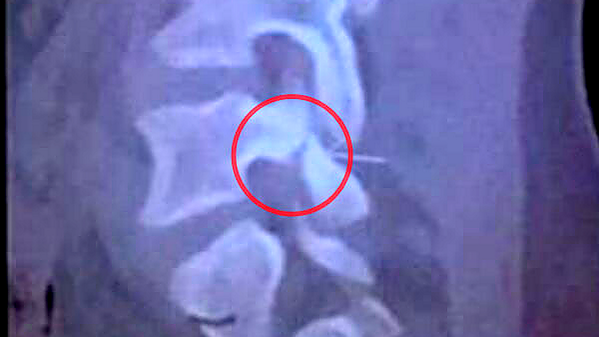

Schock-Diagnose! Röntgenbild zeigt Wirbelbruch Neymars >> focusonline.co/1ol7EPQ #Neymar #WM2014 #BRACOL